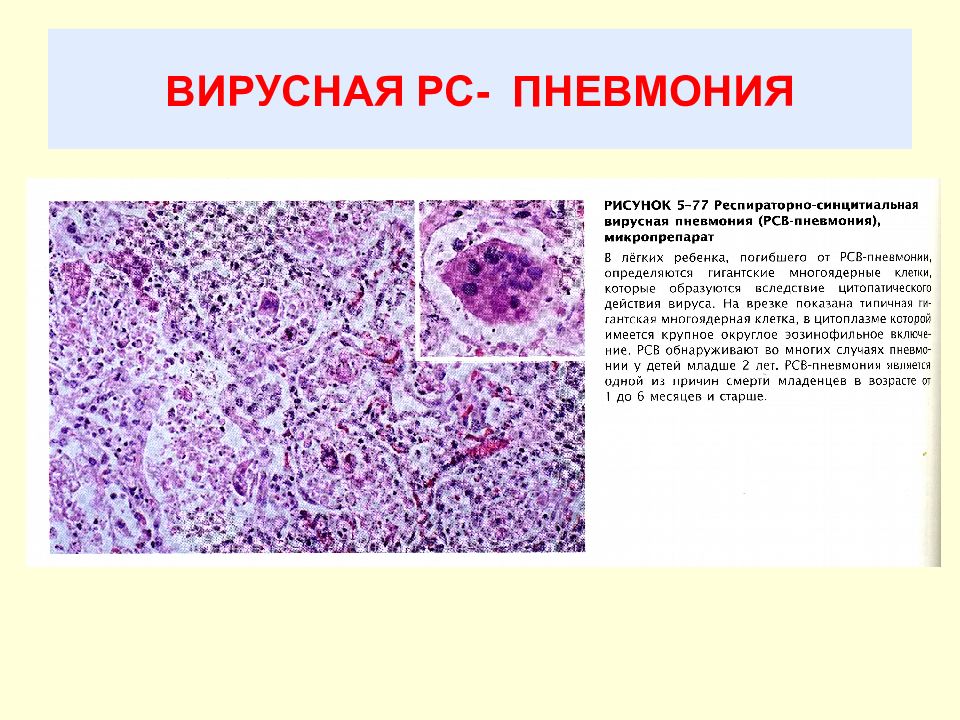

Карнификация Легкого: Микропрепараты и Диагностика

Раздел: Калейдоскоп образов